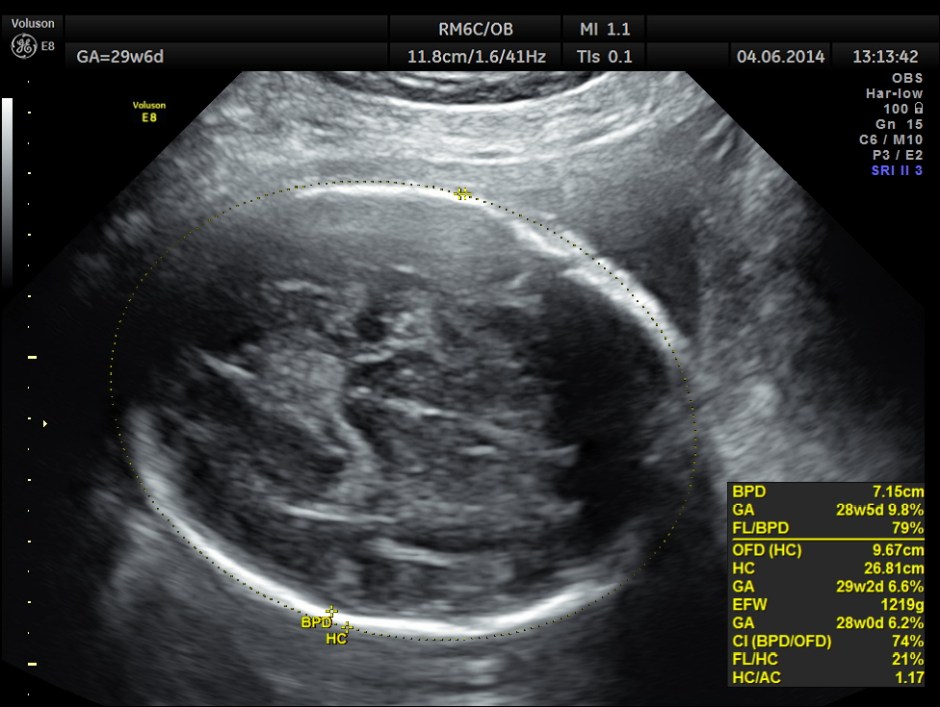

Biometric measurements show AC <2.3 %TILE

BPD , HC <10 % tile and AC is < 2.3 % tile .